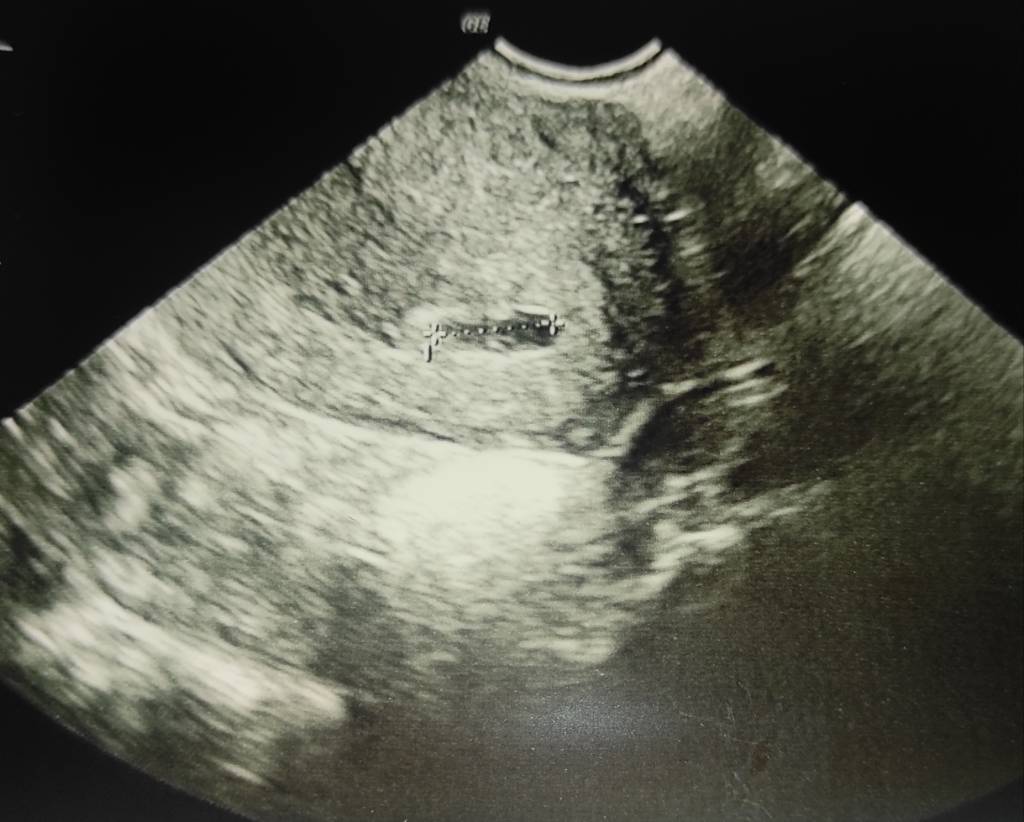

Brak pęcherzyka 5+7, HCG ponad 4000

Czy może ktoś miał taką sytuację? Nie mam żadnych plamień, krwawień, bóli.

Czy jest nadzieja że pęcherzyk pojawi się w następnym tygodniu czy może to świadczyć o ciąży pozamacicznej ?

Nie to że nie ufam tylko po prostu nie wiem co się aktualnie dzieje, martwię się bo nie mam żadnych boli ni nic a mimo wszytsko lekarz mówił że nie widzi pęcherzyka albo nie może stwierdzić czy to jest pęcherzyk ciążowy. Ufam temu lekarzowi ale muszę czekać do środy przez co mocno się stresuje